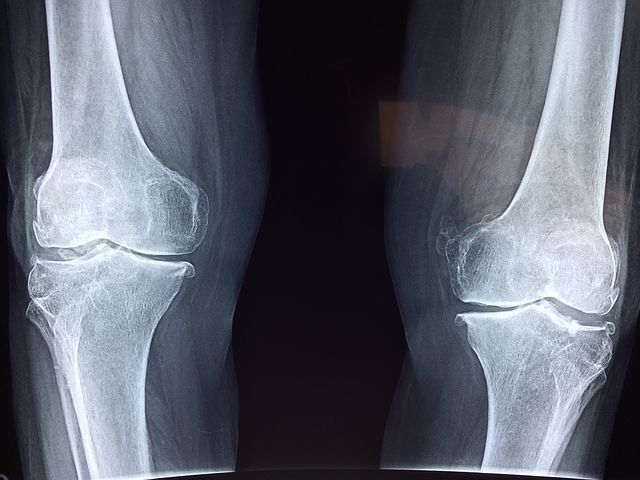

손, 발가락 같은 작은 관절에 발병하는 경우가 대부분이지만, 기간이 길어지고 치료가 늦어짐에 따라 무릎, 어깨, 허리 등 큰 관절에 염증이 전이되는 경우가 발생합니다. 완벽한 요인이 밝혀지지는 않았으나 유전, 흡연 습관, 잇몸 질환 등과 관련이 있다고 보고되고 있습니다.

변형이 심하여 일상생활에 방해가 되거나 증상이 심해 관절의 파괴를 피할 수 없는 중증 환자에게 시행됩니다. 상태에 따라 인공 관절 성형술이나 고정술 등을 고려합니다.